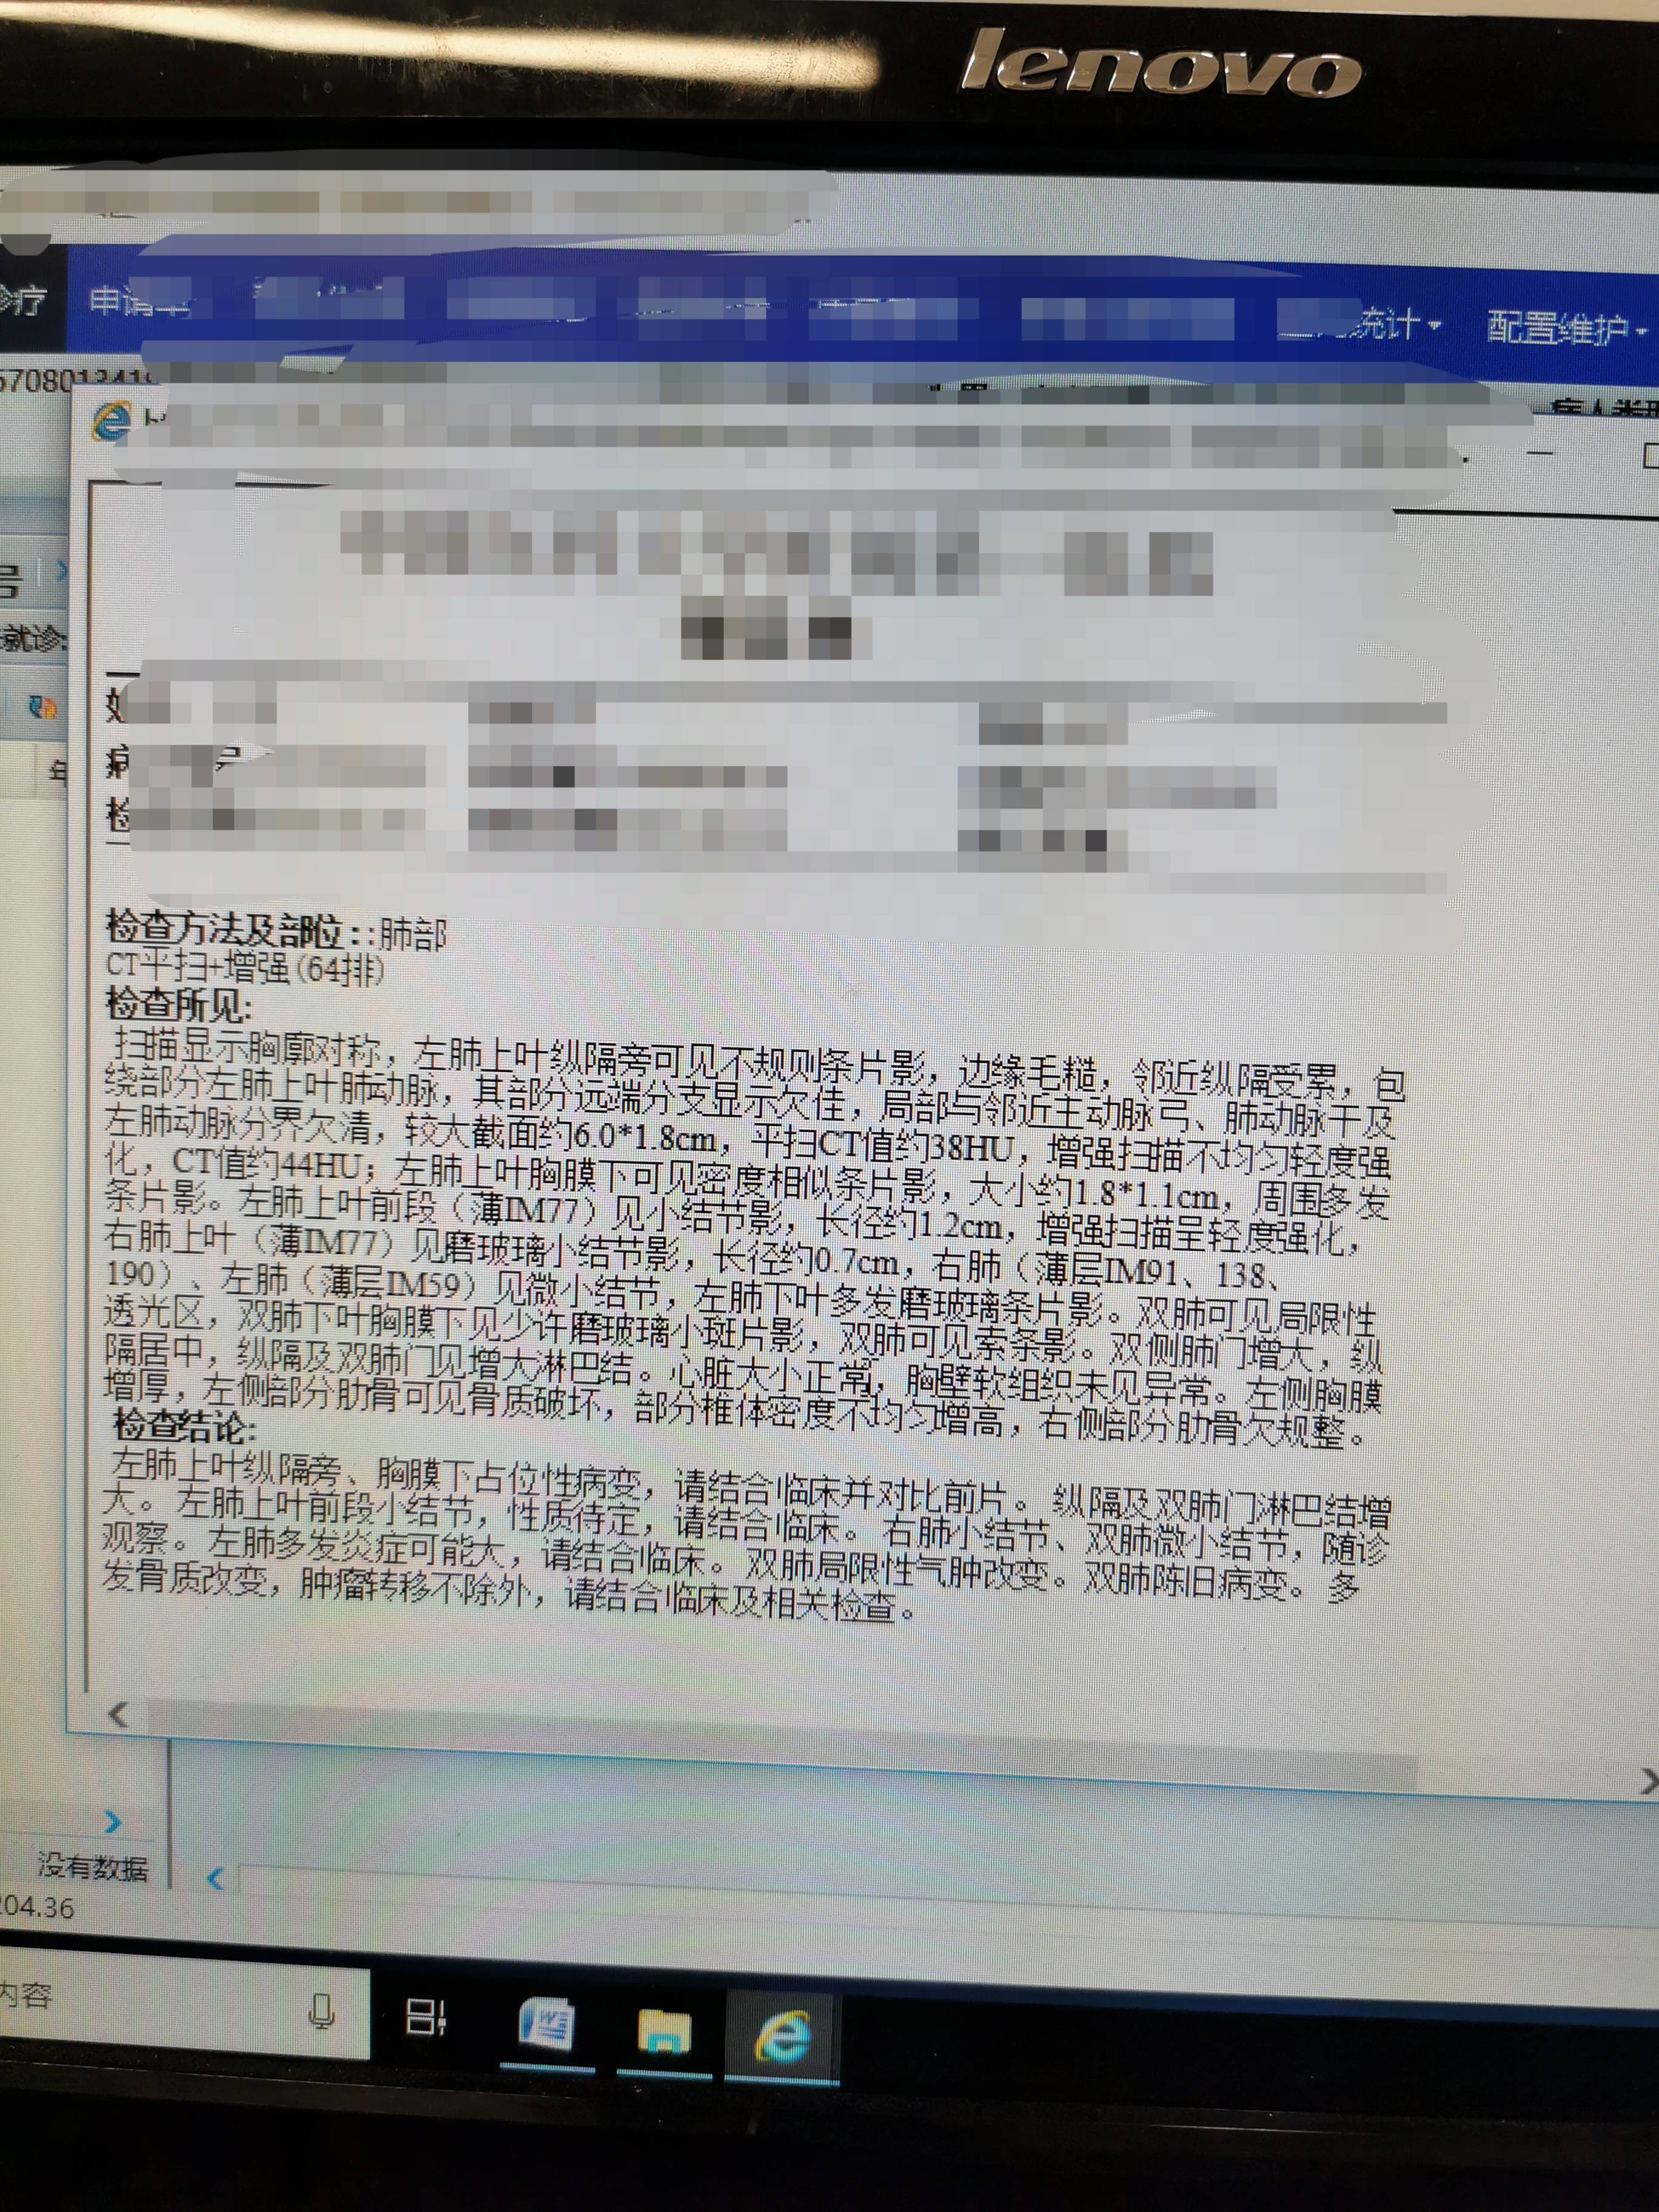

2化后肺CT结果: